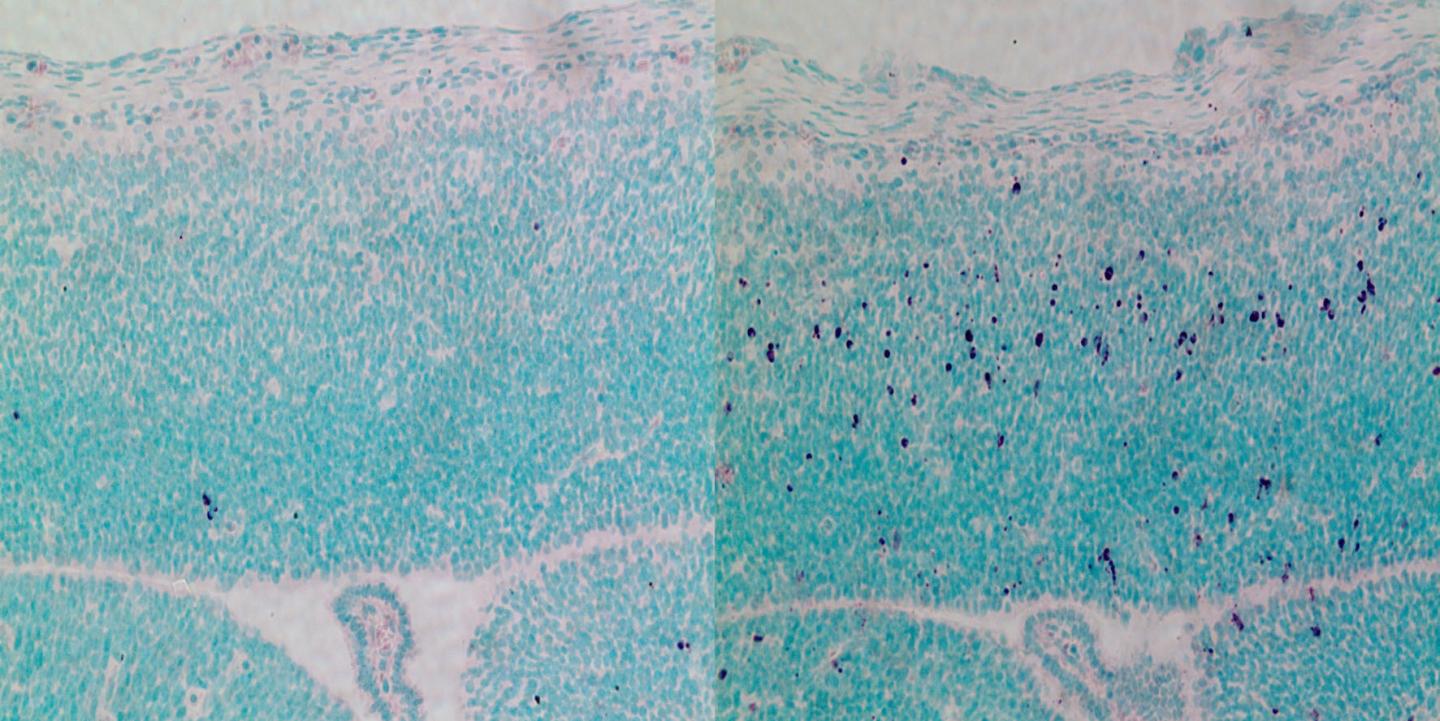

The scientists describe that this protein triggers the death of brain stem cells. This occurs because cells without CEP63 have delayed cell division, leading them to enter programmed cell death through p53. "Cell death due to mutations in CEP63 is the main cause of the brain defects. When we prevent cell death by removing p53 from developing embryos, the brain develops to its normal size," explains Jens Lüders, head of the Microtubule Organization Lab.